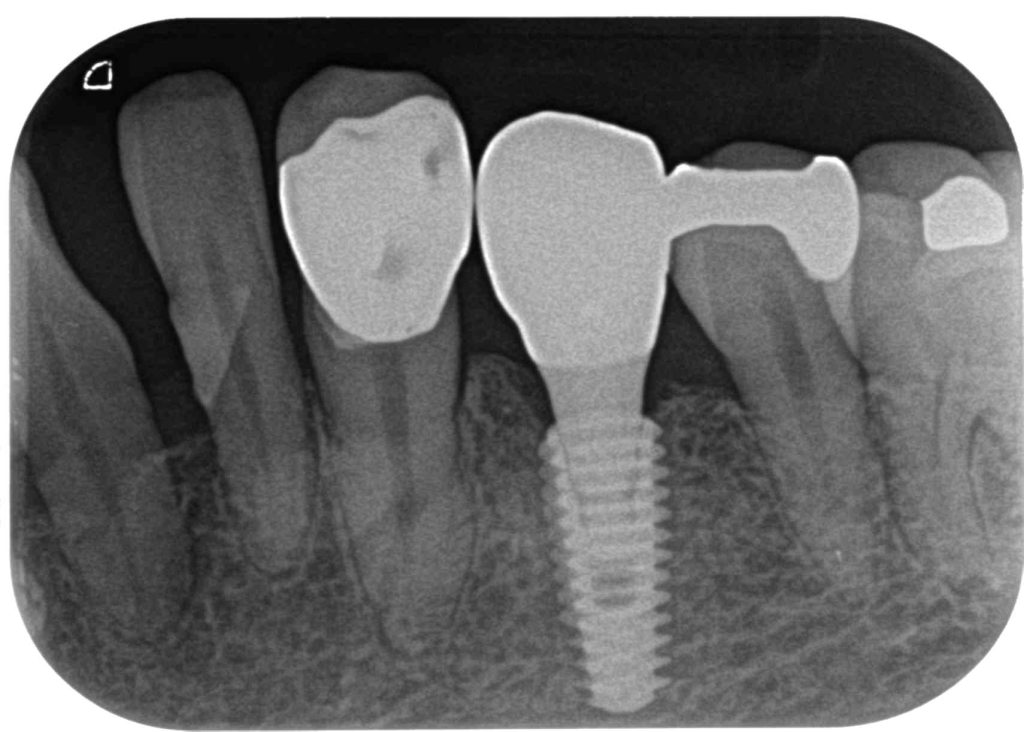

症例260代 女性 主訴 グラグラして噛めない

治療前

治療後

治療前

治療後

グラついていて奥歯でしっかり噛めないと訴え来院。

力学的に強いインプラントを選択。右下6番に埋入。

オペ後、骨との密着値も良く、約2ヶ月後には、ジルコニアを装着し終了。

リスクとしては外科的侵襲がある。デメリットは、保険外診療の為、経済的負担がある。

費用 58万(税込)(オペ・仮歯・最終補綴物まで含む)